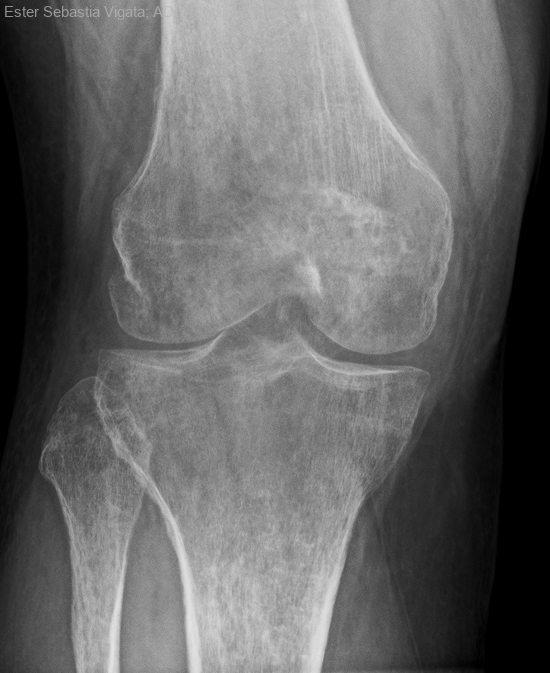

Osteoporosis transitoria del embarazo

Se trata de una mujer con antecedentes de HTA y embarazo mediante fecundación in vitro el 24.6.24.